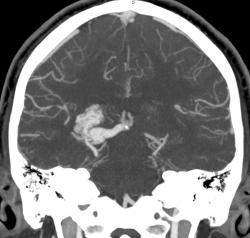

Предсталяю артериовенозную аневризму. Может кому-нибудь будет интересно.

Виден клубок неправильно развитых сосудов, питающихся от задней мозговой артерии и дренирующийся в прямой синус. Перифокальных изменений нет.

Черная стрелка - питащий сосуд - задняя мозговая артерия, зеленая - дренирующая вена к прямому синусу, красная - прямой синус.

Я чуть увеличил фрагменты изображений с "патологическим состоянием"

Очень наглядна видна сосудистая мальформация.

Питание идет из гипертрофированных задней мозговой и средней мозговой артерий (красные стрелки), дренирование в основном в верхний сагиттальный синус (синий кружок). Дренирующая вена - синие стрелки.